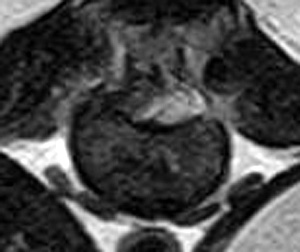

市内の先生からダックスちゃん両後肢麻痺グレード3でMRI検査及び手術依頼でご紹介がありました。MRI検査で第12‐13胸 椎間椎間椎間板ヘルニア、右側優位な圧迫と診断し即日手術となりました。→<その2>へ続く